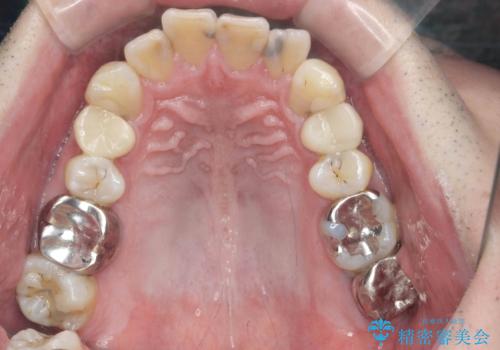

全ての銀歯を外すメタルフリー治療 + 歯並びをきれいにする矯正治療

- 今装着されている全ての銀歯の除去、虫歯の治療、矯正治療を含めた総合治療を希望され来院されました。

放置すると大きくなりそうな虫歯をまず治療、矯正治療を行ったのち、全ての銀歯を除去しセラミック治療を行う治療計画としました。